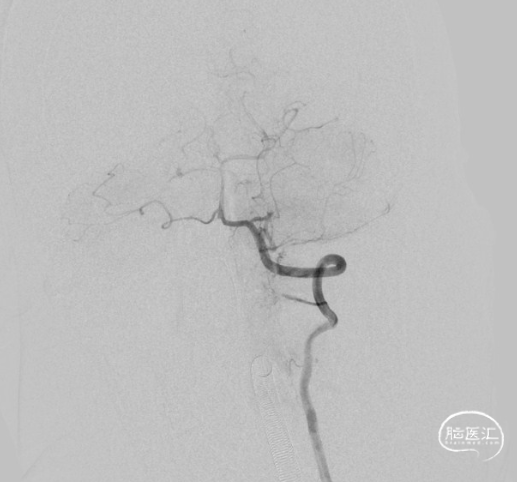

一期治疗

治疗经过